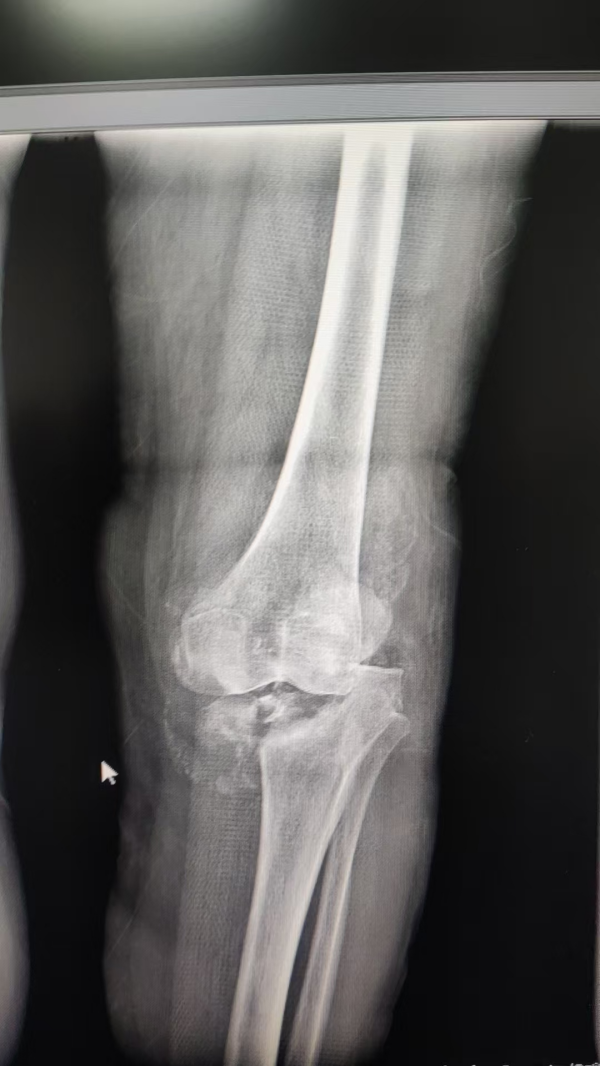

▲术前

该患者长期饱受膝关节剧痛和活动受限困扰,生活质量严重下降。入院后经系统检查,确诊为梅毒性膝关节炎。此病本就罕见,加之患者膝关节已遭严重破坏,传统疗法难以奏效,关节置换成为唯一有效选择。然而,患者合并梅毒感染的特殊情况,使得手术面临极高的感染风险、复杂的免疫反应等难题,且国内外可借鉴的成功案例极为有限。面对如此复杂的病情,我院骨关节科迅速启动多学科会诊,联合院内皮肤科、感染科、检验科、麻醉科专家,并特邀四川大学华西医院专家进行远程会诊。团队深入研讨病情,整合各学科优势,为患者量身定制了精准的治疗方案。